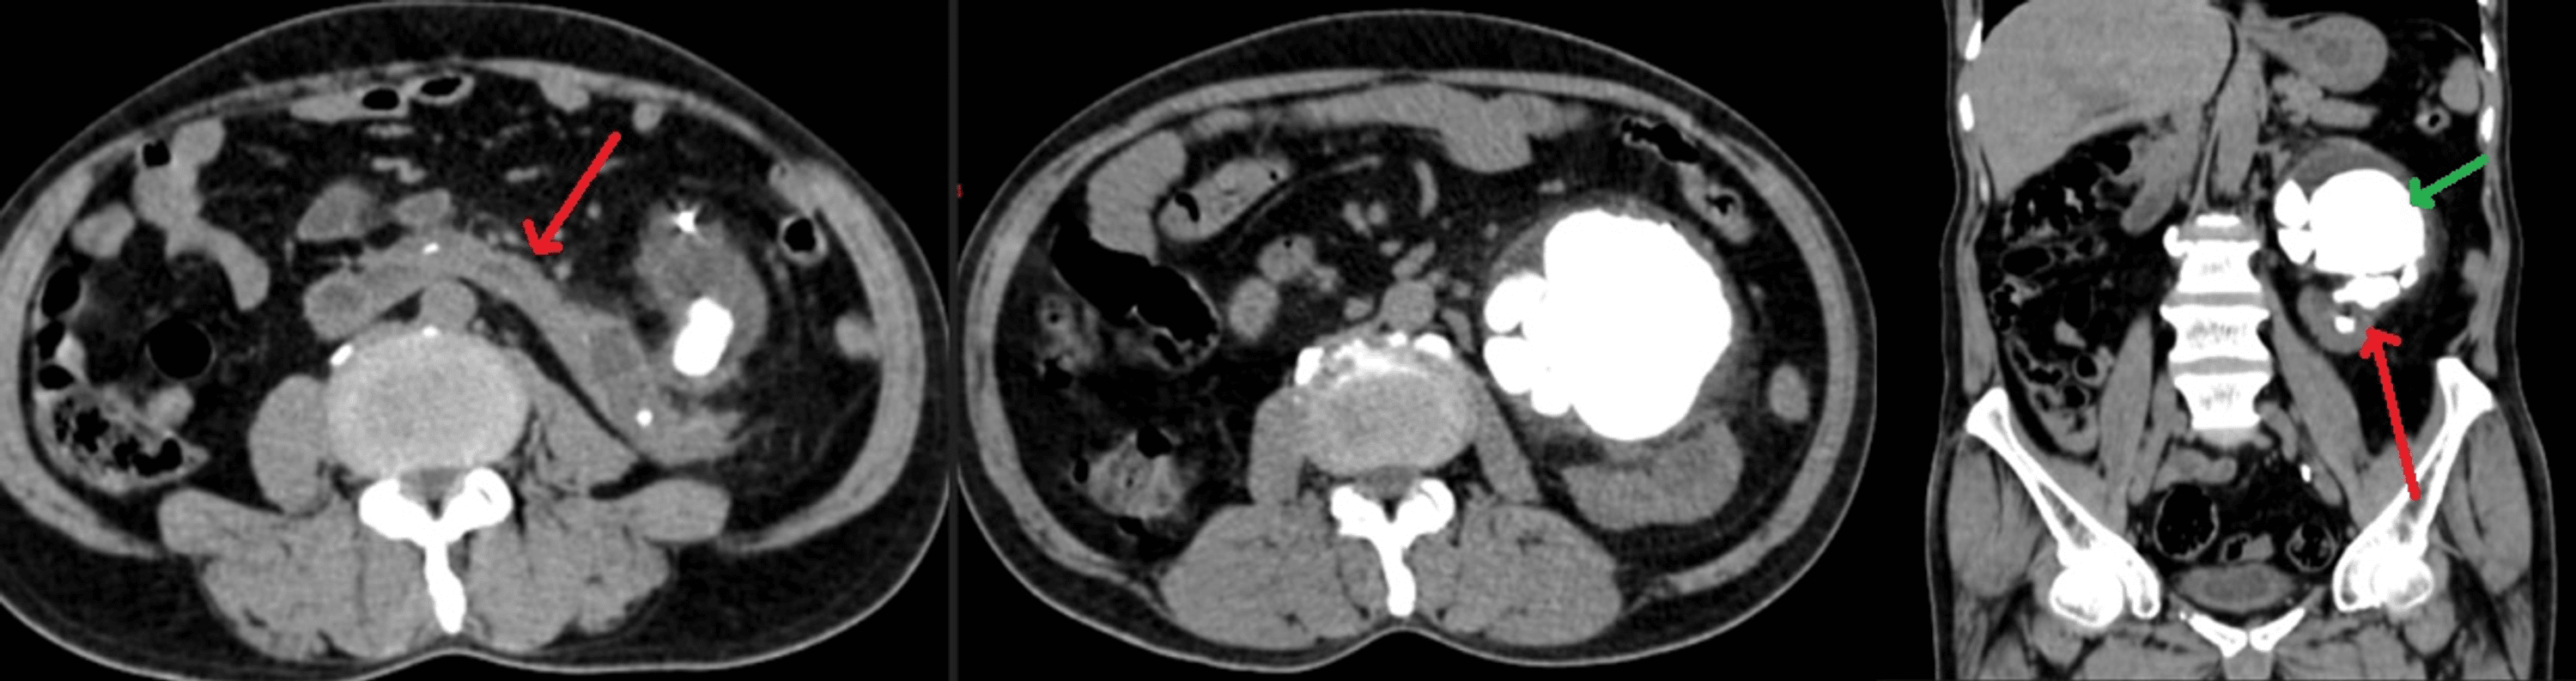

Horseshoe Kidneys with Cysts Kidney Case Studies CTisus CT Scanning Horseshoe Kidney With Cysts horseshoe kidney (hsk) is the most common renal fusion anomaly. Seven in ten people with this condition experience. — the horseshoe kidney (hsk) is the most common congenital abnormality of the upper urinary tract with an incidence. A whole range of anomalies has been known to be. They render the kidneys susceptible. — horseshoe kidneys are the. Horseshoe Kidney With Cysts.

Horseshoe Kidneys with Cysts Kidney Case Studies CTisus CT Scanning Horseshoe Kidney With Cysts — horseshoe kidney, also called renal fusion, is a condition that starts before a child is born. — horseshoe kidney (renal fusion) is when a person is born with the kidneys fused together. horseshoe kidney (hsk) is the most common renal fusion anomaly. — horseshoe kidneys are the most common fusion defect of the kidneys, but. Horseshoe Kidney With Cysts.

Horseshoe Kidneys with Cysts Kidney Case Studies CTisus CT Scanning Horseshoe Kidney With Cysts — horseshoe kidney (renal fusion) is when a person is born with the kidneys fused together. — horseshoe kidney, also called renal fusion, is a condition that starts before a child is born. Seven in ten people with this condition experience. horseshoe kidney (hsk) is the most common renal fusion anomaly. They render the kidneys susceptible. As. Horseshoe Kidney With Cysts.

Horseshoe Kidneys with Cysts Kidney Case Studies CTisus CT Scanning Horseshoe Kidney With Cysts — the horseshoe kidney (hsk) is the most common congenital abnormality of the upper urinary tract with an incidence. They render the kidneys susceptible. As a baby develops in the. — horseshoe kidney (renal fusion) is when a person is born with the kidneys fused together. Horseshoe kidneys are the most common type of renal fusion anomaly. . Horseshoe Kidney With Cysts.